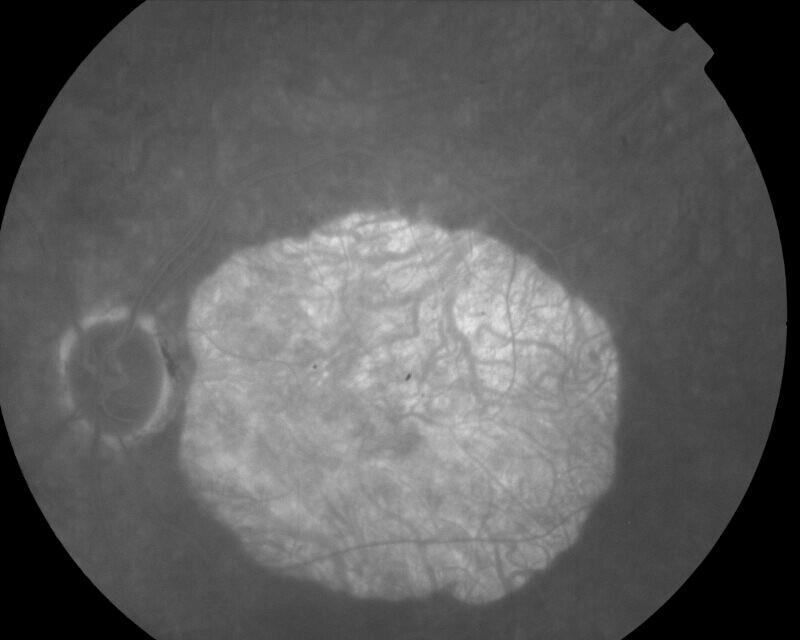

CICATRICE APRES EXERESE CHIRURGICALE DE NEOVAISSEAUX

IM000009.JPG